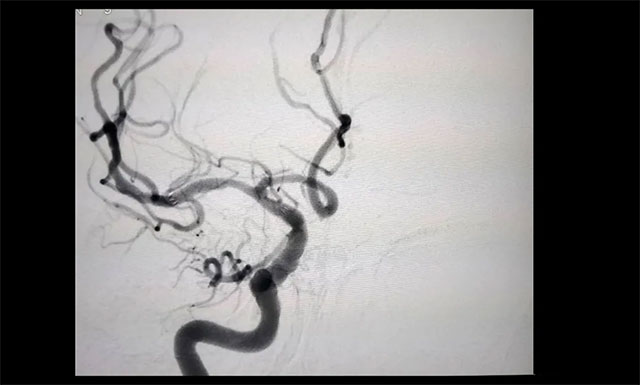

▲ 患者右侧大脑中动脉M1段重度狭窄

经行 DSA 检查,胡老伯右侧椎动脉纤细,右侧大脑中动脉 M1 段重度狭窄(约80%-90%),只剩下不到20%的空间,血流明显受阻。李振并主任表示,大脑中动脉是颈内动脉的延续,它供应大脑外侧面3/4的血液,所以大脑中动脉狭窄后会导致部分区域血流不足而引起相关症状。严重时会出现偏身运动障碍、偏身感觉障碍,甚至昏迷。一般情况下,当大脑中动脉狭窄程度超过70%,需要及时进行支架植入治疗,同时要注意其他危险因素的预防。